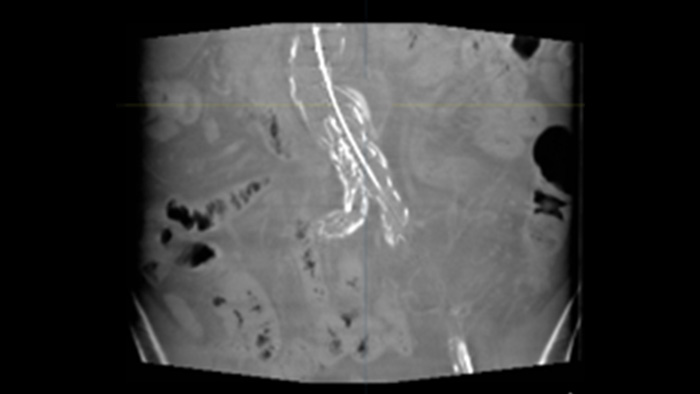

SmartCT Soft Tissue ist eine Röntgen-Erfassungstechnik, die eine CT-artige Darstellung des Weichgewebes in Relation zu anderen Strukturen erzeugt. Sie kann direkt am Tisch über den Touchscreen gesteuert werden. Mit den CT-artigen Bildern können Weichgewebe, Knochenstrukturen und Stent-Platzierung beurteilt werden.